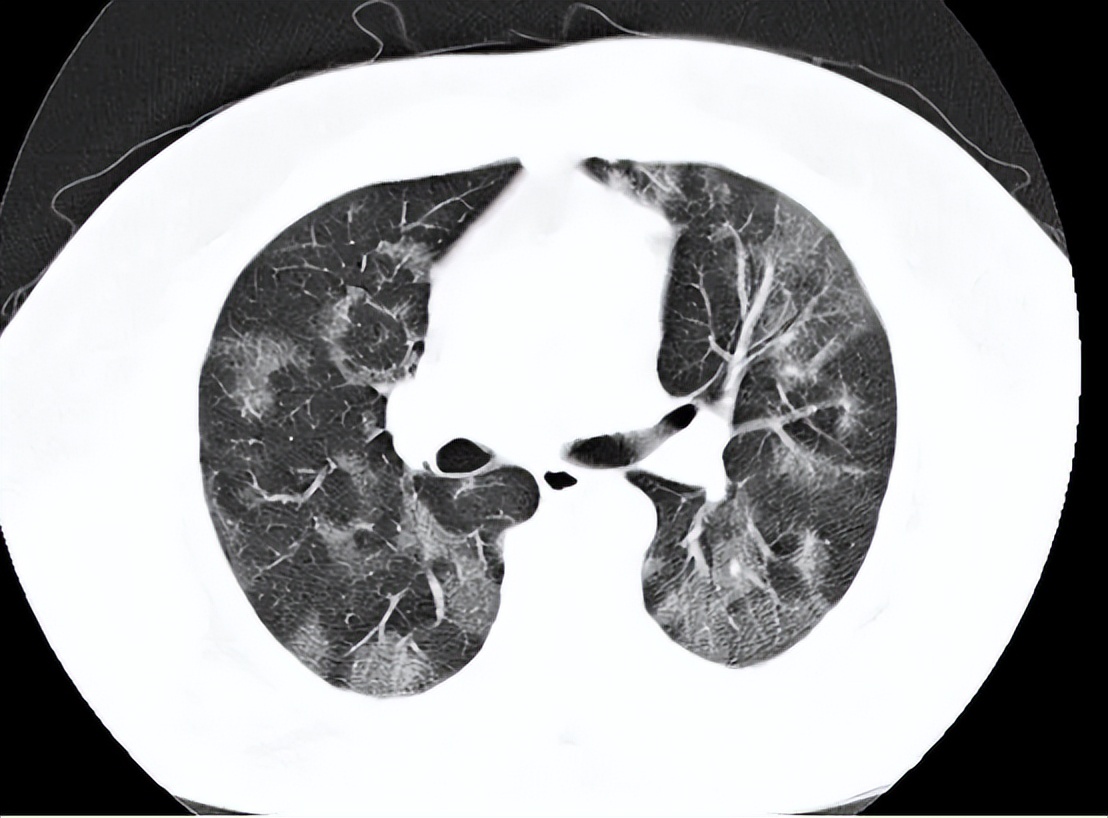

在肺部这项技术最初主要用于支气管镜下腔内病变的活检。弥漫性实质性肺疾病的病因诊断及肺外周局部病变的活检,也用于代替传统的经支气管镜钳夹活检来监测肺移植后的排斥反应情况。

在支气管镜下肺活检中,冷冻获得标本可达普通活检钳的4倍左右,取得的组织结构也更完整,最大限度接近疾病的原始病理状态,总体来说取得的标本质量明显高于常规钳。

胸腔镜下胸膜活检是诊断不明原因胸腔积液的主要方法,可以用硬质或半硬质胸腔镜进行。半硬质胸腔镜与柔性支气管镜相似,技术相对简单,操作较容易的特点,同时因机械强度低,造成活检得到的标本小活检深度浅。

有些疾病,比如胸膜间皮瘤或者胸膜纤维化,胸膜广泛增厚、纤维化明显,这样的情况下,使用半硬质胸腔镜行常规活检钳活检,得到的标本不理想且很耗时,这时候需要采用其他更好的办法来进行胸膜活检。

但是冷冻活检可以克服常规钳的局限性,提供更大的样本更深、挤压伪化。对获取的组织标本提出了更高的需求。胸膜冷冻活检由于能获得更大更深的组织,以及更少的挤压伪影等优点有利于免疫组化、基因测序等方面的分子研究,更好的服务于临床。